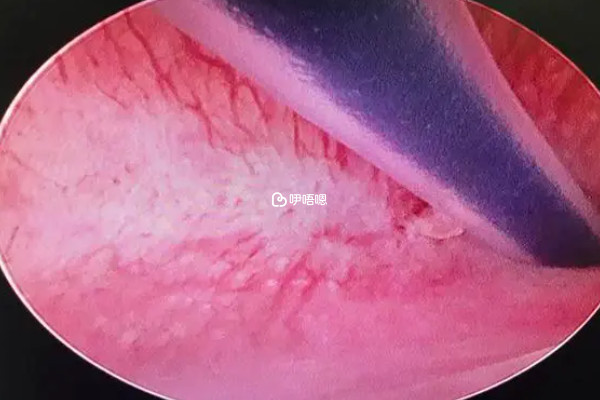

進行宮腔鏡清宮手術的時候需要打麻藥,因為清宮手術是使用手術器具進入到女性的子宮裡面進行操作,在手術的過程當中,會產生比較明顯的疼痛症狀,如果患者身體扭動,可能會導致清宮不徹底或者手術損傷,在清宮手術的時候打麻藥能夠減少此類風險的發生。

但也有有部分女性由於各種原因,可能會選擇不打麻藥,需要進行具體的分析,比如有部分女性對於疼痛的耐受程度比較高、身體對麻藥不耐受或者經濟原因等,可能會選擇不打麻藥就進行清宮手術,而如果女性比較怕疼也可以要求醫生打麻藥,而關於是選擇區域性麻醉還是全身麻醉要注意這些事項: